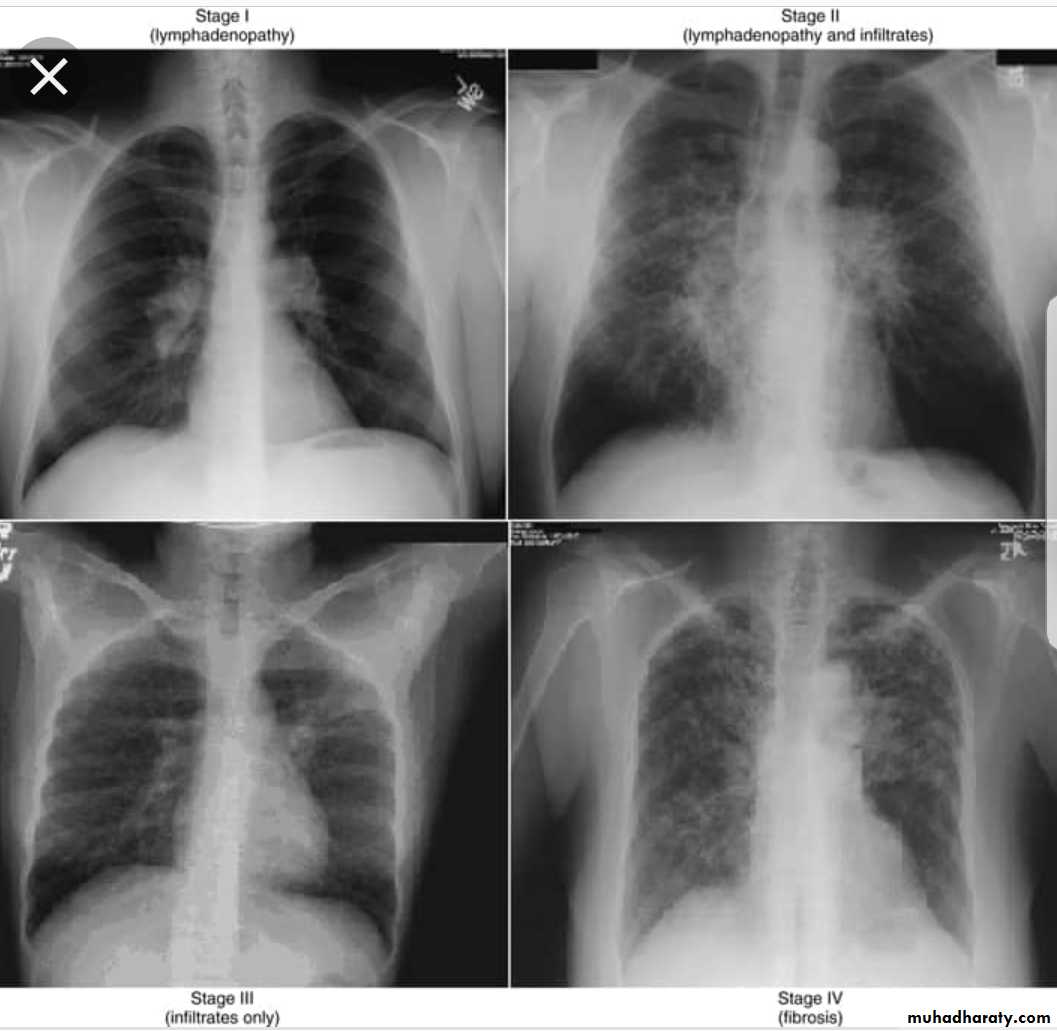

Sarcoidosis

Chronic granulomatous disease of unknown etiology.

Rare in our locality.Has a chronic coarse with relapse & remision

Affect skin, l.n., bone, lung, etc…Microscopically

non-caseating epitheloid granuloma. The giant cell contain calcified bodies (Schaumanns bodies)Diagnosis

Clinical.Skin test (Kviem test): intradermal injection of sarcoid tissue. In 4 weeks, nodule develops, has a sarcoid appearance.

Biopsy.